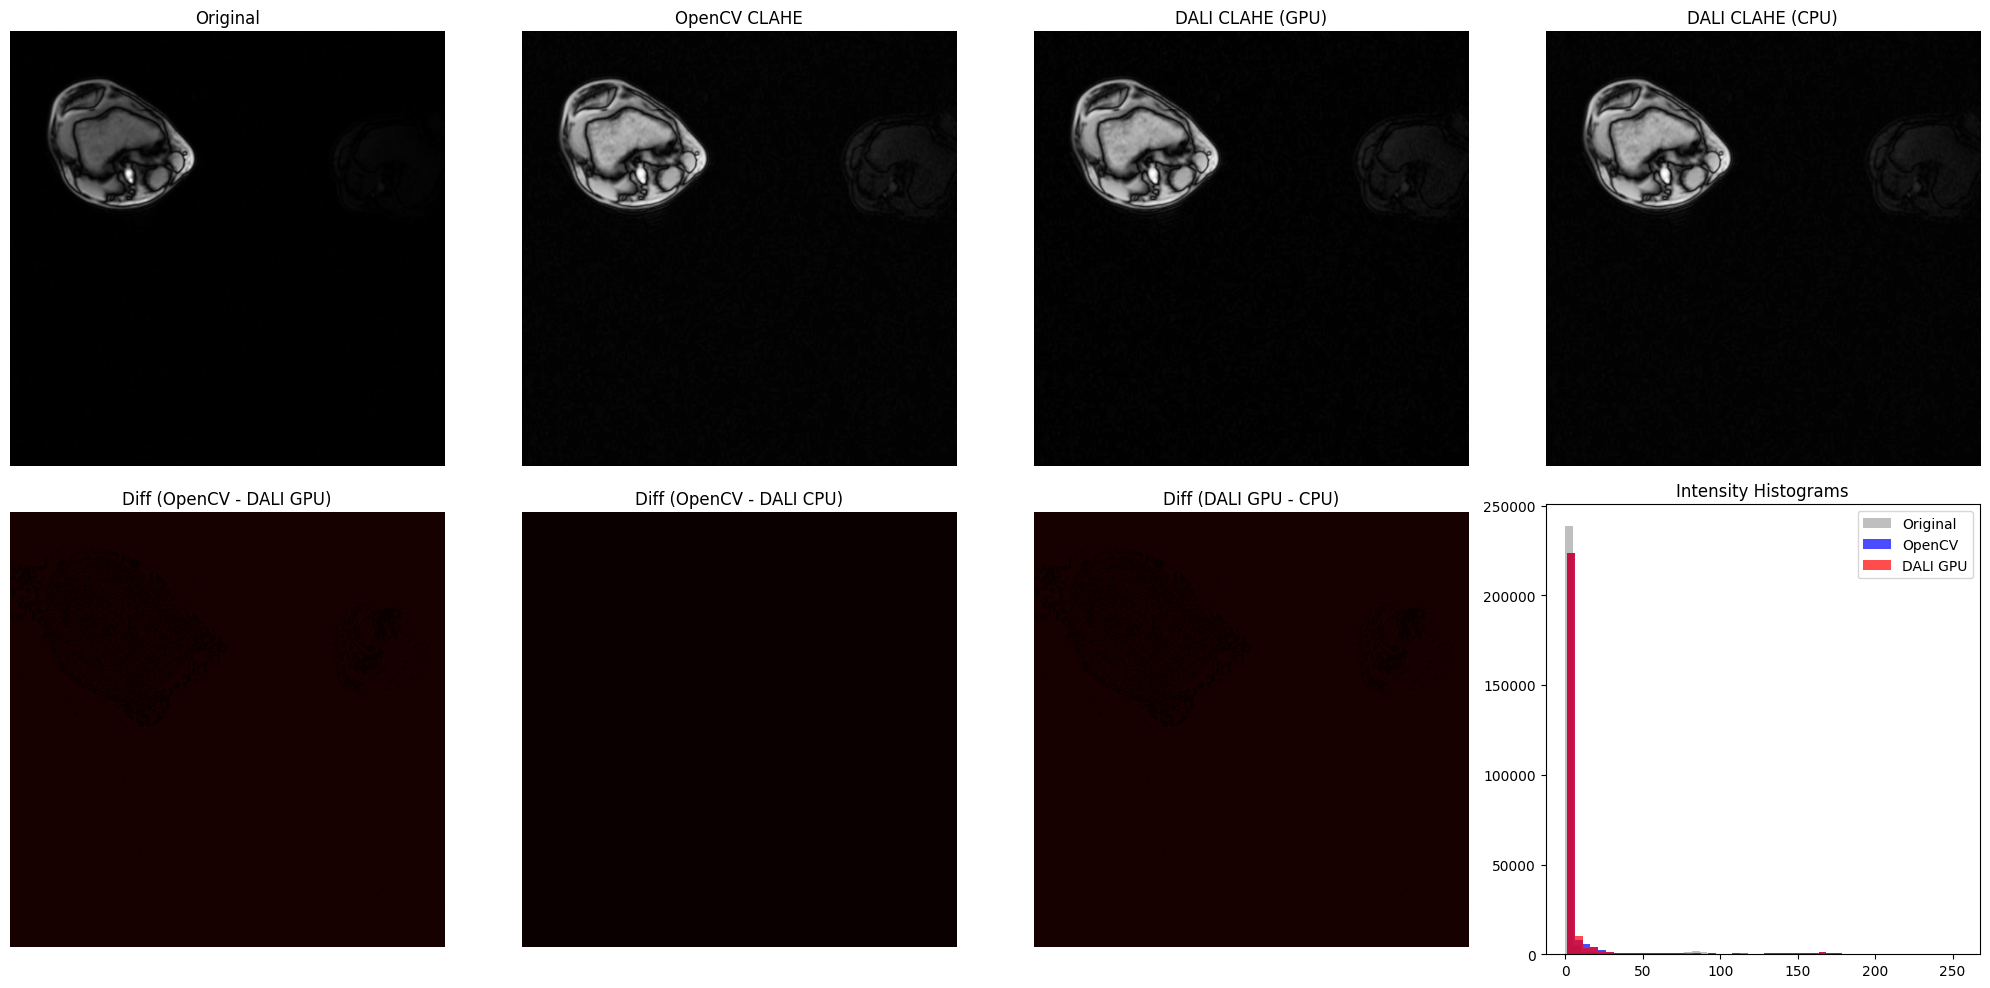

DALI CLAHE vs OpenCV CLAHE on Medical Imaging (Knee MRI)#

This section demonstrates CLAHE on real low-contrast medical imaging data - knee MRI slices from the DALI_extra repository. Medical imaging is where CLAHE truly shines, as these images often have naturally low contrast that benefits significantly from adaptive histogram equalization.

print("\nImplementation Comparison Metrics:")

print(f"OpenCV vs DALI GPU:  MSE = {mse_ocv_gpu:.4f}, MAE = {mae_ocv_gpu:.4f}")

print(f"OpenCV vs DALI CPU:  MSE = {mse_ocv_cpu:.4f}, MAE = {mae_ocv_cpu:.4f}")

print(f"DALI GPU vs CPU:     MSE = {mse_gpu_cpu:.4f}, MAE = {mae_gpu_cpu:.4f}")

print("\nNote: Lower values indicate closer agreement between implementations.")

../../../_images/examples_image_processing_clahe_dynamic_mode_11_0.png

Implementation Comparison Metrics:

============================================================

OpenCV vs DALI GPU:  MSE = 0.9326, MAE = 0.9325

OpenCV vs DALI CPU:  MSE = 0.0000, MAE = 0.0000

DALI GPU vs CPU:     MSE = 0.9326, MAE = 0.9325

Note: Lower values indicate closer agreement between implementations.

[7]:

# Difference Maps and Intensity Histograms

fig, axes = plt.subplots(2, 4, figsize=(20, 10))

# Bottom row: difference maps and histogram

# Intensity histograms

axes[1, 3].set_title("Intensity Histograms")

../../../_images/examples_image_processing_clahe_dynamic_mode_12_0.png